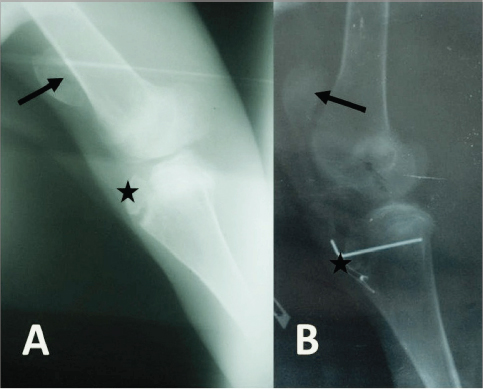

Radiographically, the stifle areas of the affected goats showed ventrocaudal PL in three cases (Figs. 2 and 3) and dorsal PL in the other two cases, for which surgical treatment was performed (Fig. 4A).

Surgical incision of the stifle joint revealed an almost flat trochlear groove suggesting trochlear ridge hypoplasia. Surgical correction of luxated patella showed satisfactory results in only one case but not with the other. This doe was 6 months old with grade IV lateral PL. Immediately after surgery, the stifle joint was moving in a normal way, and the doe was able to bear weight on the treated leg. Ten days postsurgery, the doe walks normally, and the wound made complete healing. Phone call follow-up 1 year later revealed that the doe did well, gave birth once and got pregnant again. The other goat was a 2-year-old buck with approximately 50 kg body weight. In this case, the surgical incision revealed a normal trochlear groove and only three surgical procedures were performed; namely, joint capsule imbrication, joint capsule release, and TTT. The correction of the luxated patella was difficult in this case. The surgical suture was ruptured, and the pin fixation had broken once the buck stood on the operated leg.

Fig. 4. (A) Mediolateral radiograph of the right stifle of a 10-month-old goat showing a dorsal PL (arrow) with no signs of trochlear ridge hypoplasia. There is also an avulsion fracture of the tibial tuberosity (star). (B) Mediolateral radiograph of the right stifle of the same goat immediately postsurgery showing that the patella (arrow) and the tibial tuberosity (star) are placed almost at their normal anatomical locations.